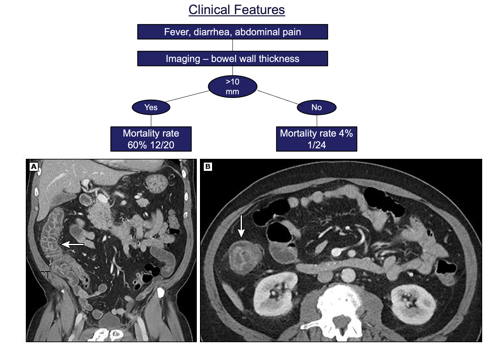

Neutropenic Enterocolitis (Typhlitis)

Figure 22: CT findings in neutropenic enterocolitis showing bowel wall thickening

Key features:

• Fever, abdominal pain, diarrhea

• Right lower quadrant tenderness

• CT: Bowel wall thickening (primarily cecum and ascending colon)

Management:

• Broad-spectrum antibiotics including anaerobic coverage

• Bowel rest, NG suction if obstruction

• Surgery only for perforation or hemorrhage